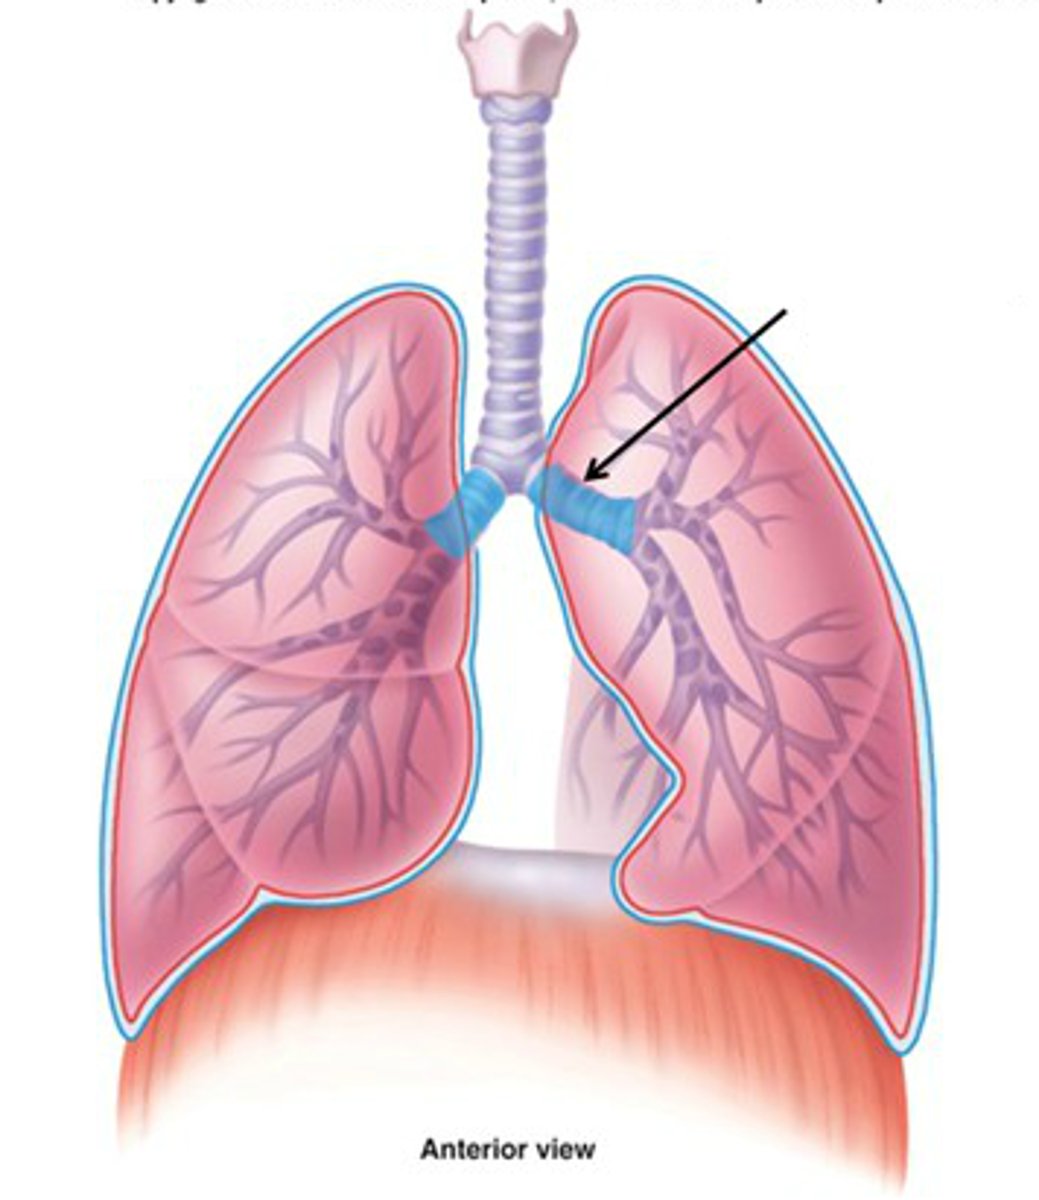

primary bronchi

The first branches of the trachea. There are two primary bronchi, one for each lung.

secondary bronchi

branches of the primary bronchi that lead to each lobe of the lung; also called lobar bronchi

tertiary bronchi

branches of the secondary bronchi that divide into bronchioles; also called segmental bronchi

bronchioles

smallest branches of the bronchi